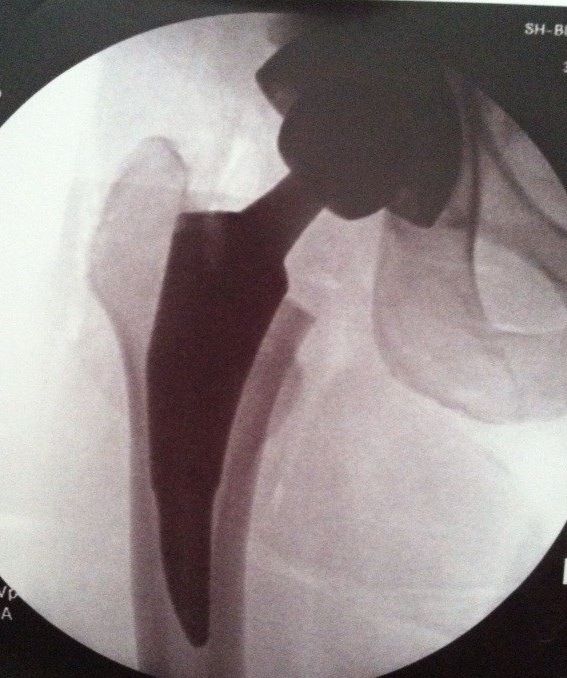

Just days before I was to undergo my hip replacement, this arrived in the mail.

Acting Captain’s Blog, First Officer Reporting: The captain has been relieved of duty by the medical officer. We arrived at the planet Spectrum for a brief layover to augment the captain’s hyperdrive by installing a new dilithium crystal stabilizer.*

*In other words, to have an anterior hip replacement—dilithium crystal stabilizer sounds much cooler, doesn’t it?